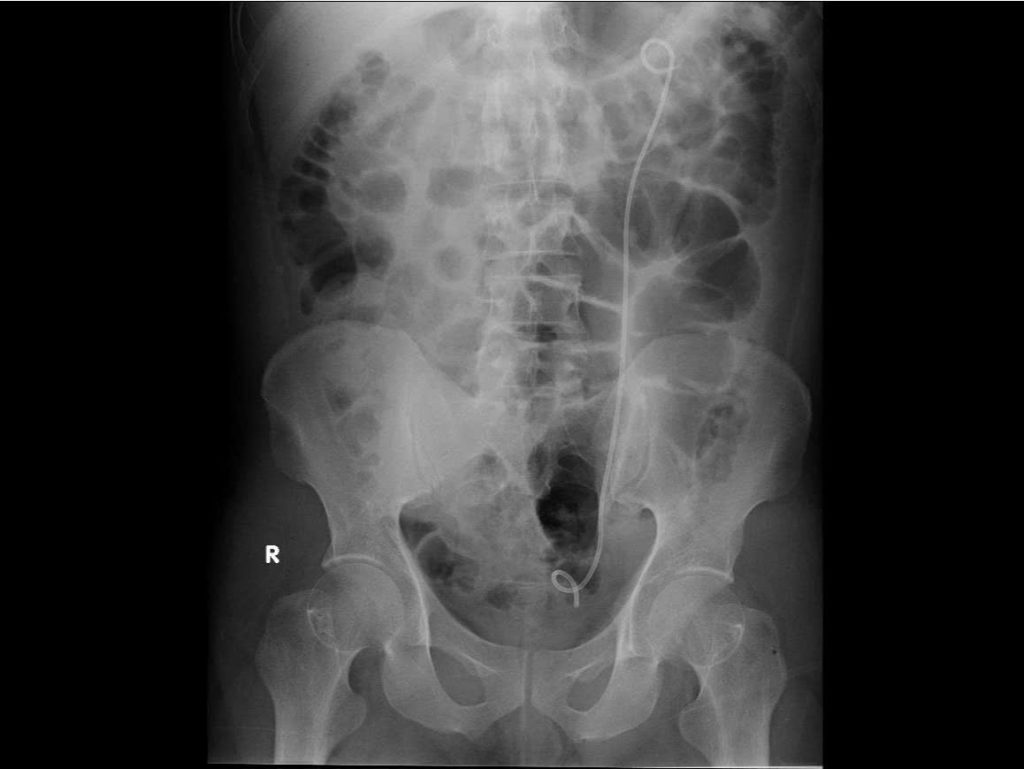

Ê- kíp các bác sĩ khoa Ngoại Tiết Niệu Bệnh viện Đa khoa Xuyên Á và các bác sĩ cấp cứu đã nhanh chóng vừa hồi sức vừa chỉ định đặt thông JJ cấp cứu từ bể thận trái xuống niệu quản và bàng quang. Thủ thuật này nhằm giải phóng chỗ tắc nghẽn do sỏi, giúp nước tiểu và mủ trong thận được dẫn lưu ra ngoài, giảm áp lực và kiểm soát ổ nhiễm trùng. Trong quá trình can thiệp, ê – kíp ghi nhận mủ chảy nhiều từ thận xuống bàng quang. Mủ được cấy để phân lập vi khuẩn giúp điều trị kháng sinh theo đúng loại vi khuẩn gây bệnh. Trong lúc chờ đợi kết quả các bác sĩ cũng sử dụng kháng sinh theo phác đồ điều trị nhiễm khuẩn nặng.

Hình ảnh cận lâm sàng sau khi đặt Sonde JJ dẫn lưu